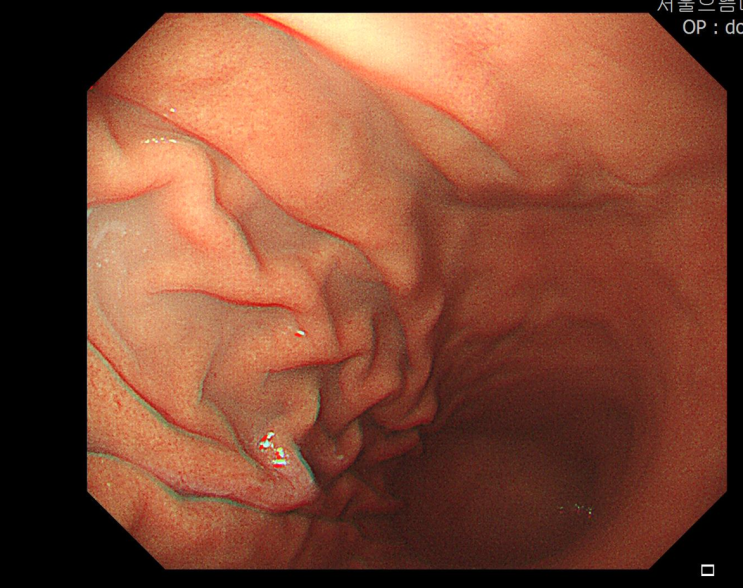

[행당동 위내시경]서울으뜸내과, 위내시경에서 발견된 위말트림프종 MALTOMA

#위말트림프종 #행당동위내시경 #서울으뜸내과 #도선동위내시경 #왕십리위내시경 #금호동위내시경 #성수동...